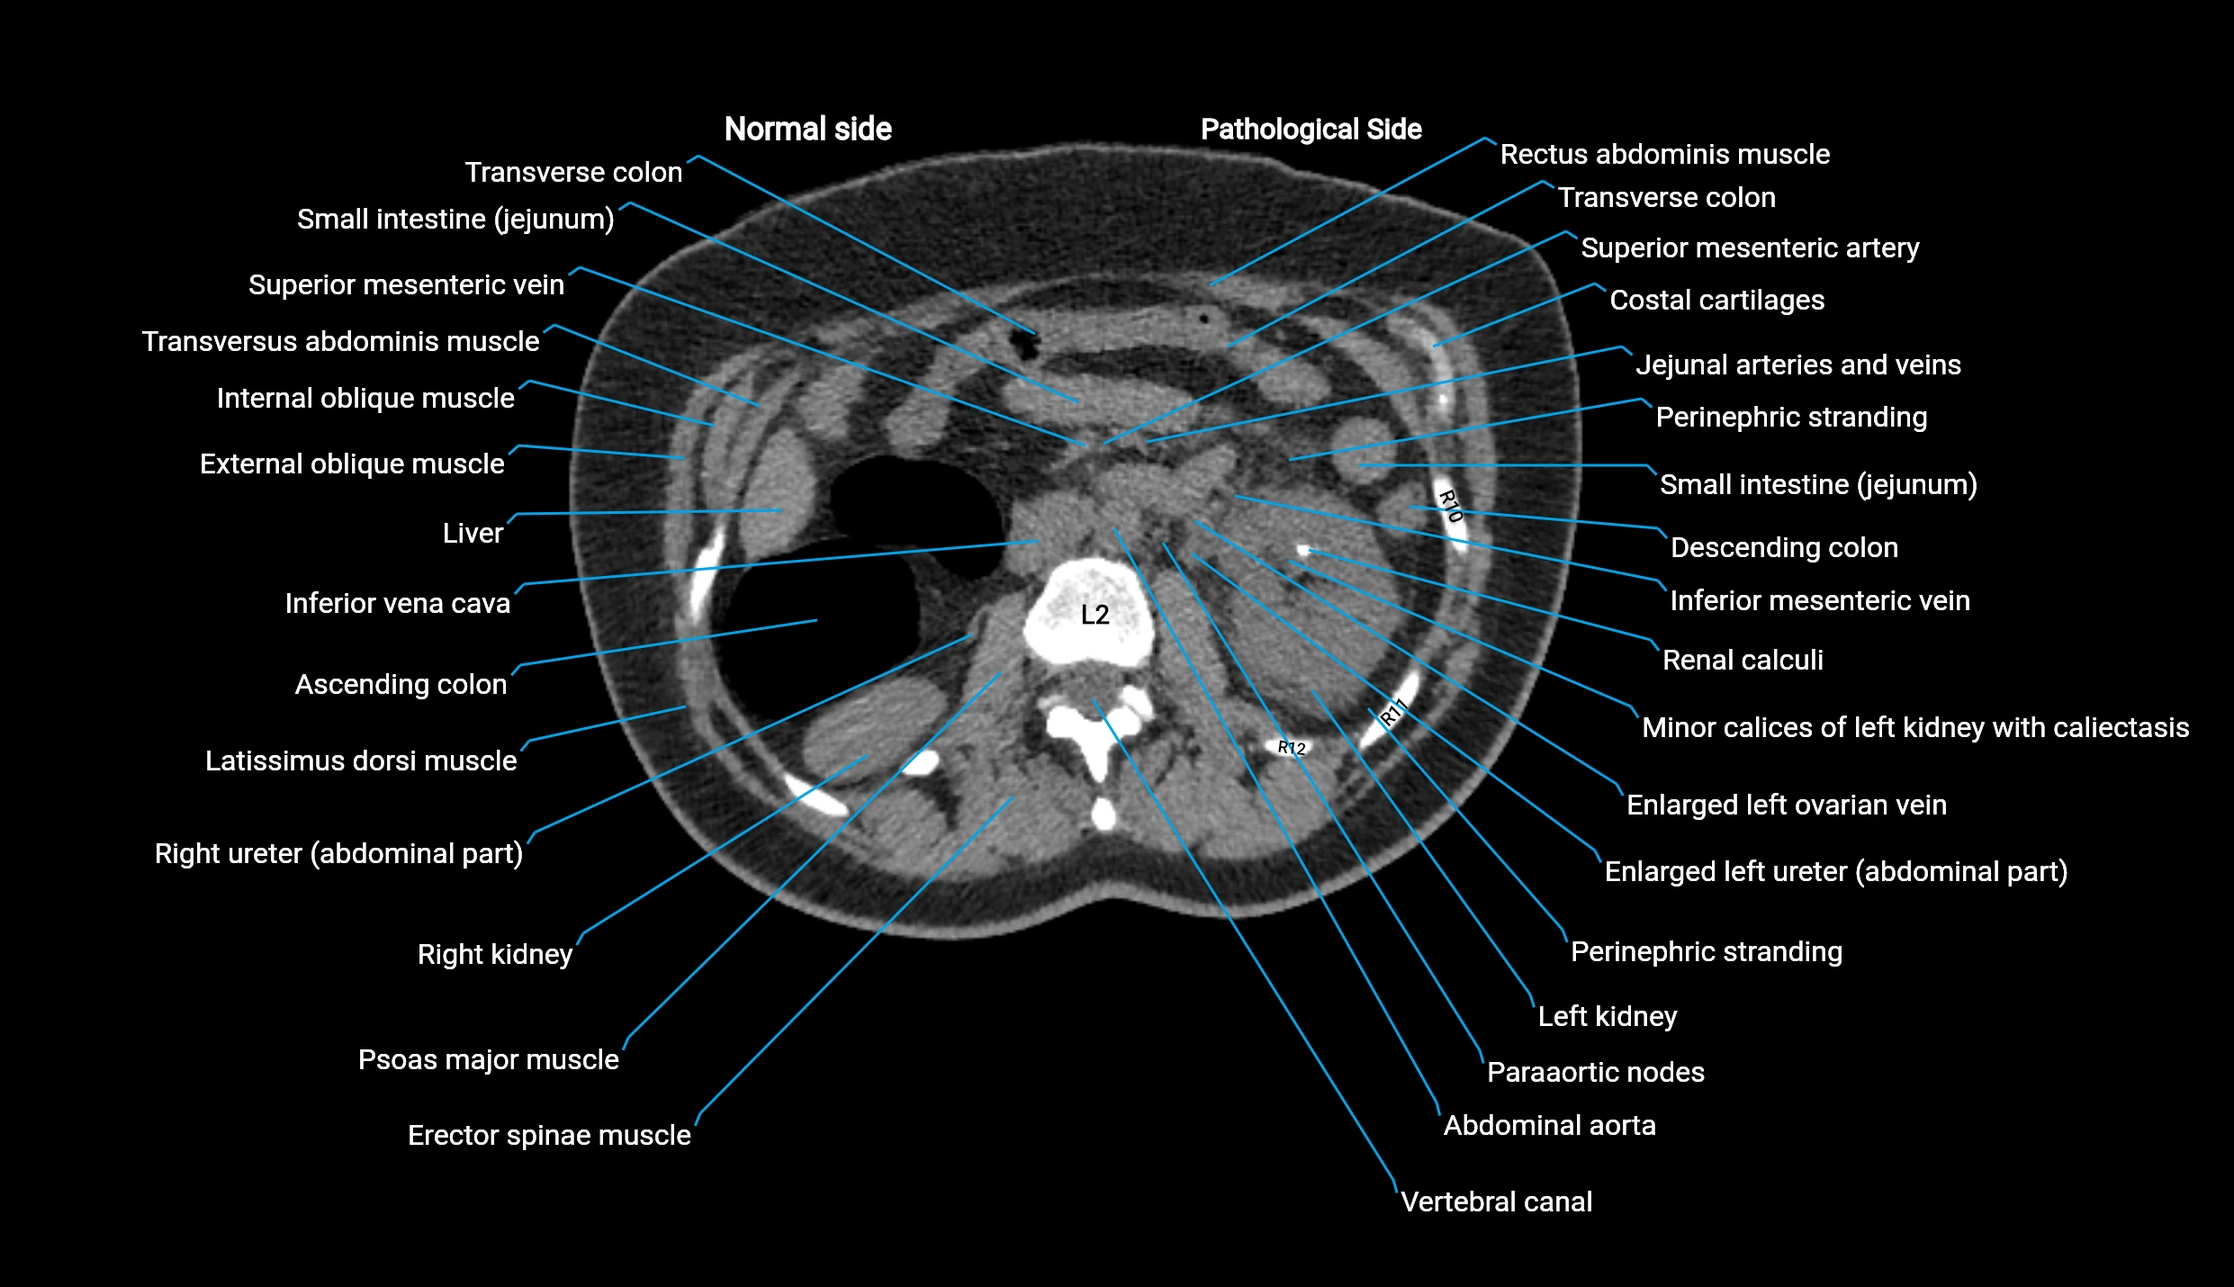

CT image

image